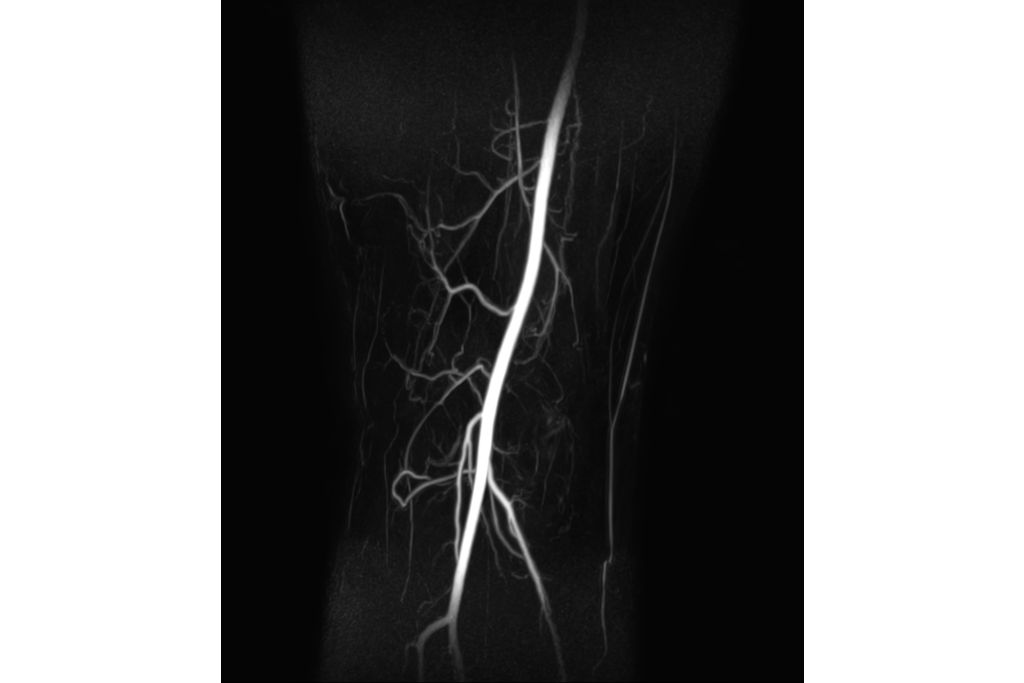

• Non-CE MRA (3D TOF)

Non-CE MRA (3D TOF)

• CE MRA

CE MRA